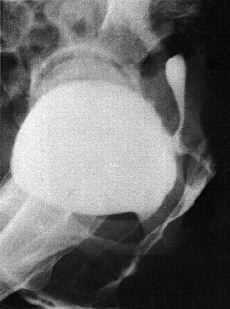

Para el diagnóstico sepracticó fundamentalmente cistoscopia yuretrocistografía o histerosalpingografía, aunque enla paciente 6 se precisaron otras exploraciones complementariascomo urografía intravenosa, TAC, enema opaco ytránsito gastroduodenal (Figs. 1 y2). A pesar de todo en esta paciente no se llegó aldiagnóstico de una fístula vesicocervical sobrecérvix restante posthisterectomía subtotal hasta elmomento de la intervención quirúrgica, con posteriorconfirmación en la anatomía patológica alobservarse la presencia de glándulas endometriales incluidasen la pared vesical

Figura2. Cistografía en la que se observa la repleción dela cavidad uterina.

En definitiva, eldiagnóstico de la fístula que nos ocupa debeconsiderarse cuando una paciente con antecedente de cesáreapresente escape involuntario de orina y/o hematuria, cíclicao no. Un parto vaginal ocurrido con posterioridad a lacesárea no excluye la posibilidad de que exista unafístula vesicouterina. El método más apropiadopara la investigación de la fístula es lacombinación de cistoscopia y cistografía, aunque larealización de pielografías nos permitirávalorar la integridad de los uréteres. Lascistografías practicadas semejan en ocasiones verdaderashisterografías tal y como hemos mostrado en la figura2.